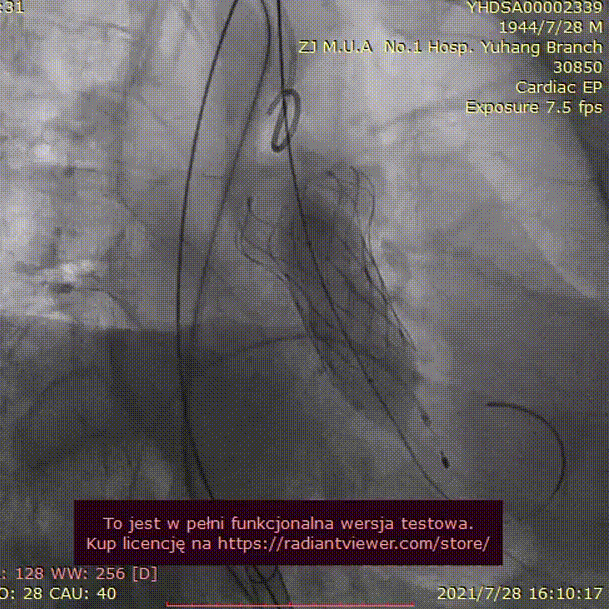

病例2 - 烟囱支架冠脉保护下 Type 0 型二叶瓣

男性,77岁,因“活动后胸闷气促”1月入院。

手术难点及策略:

该病例为Type-0 型二叶瓣,瓣叶长度较长,右冠冠脉风险高,拟在冠脉保护下行TAVR,拟23mm球囊预扩,植入TAV 24号瓣膜。

手术过程:

23mm球囊预扩

(有腰征,无瓣周漏,右冠开口阻塞)

TAV24 瓣膜释放前定位

释放4.0*30mm烟囱支架

植入后造影

术后压差1mmHg

术中经食道心超评估: